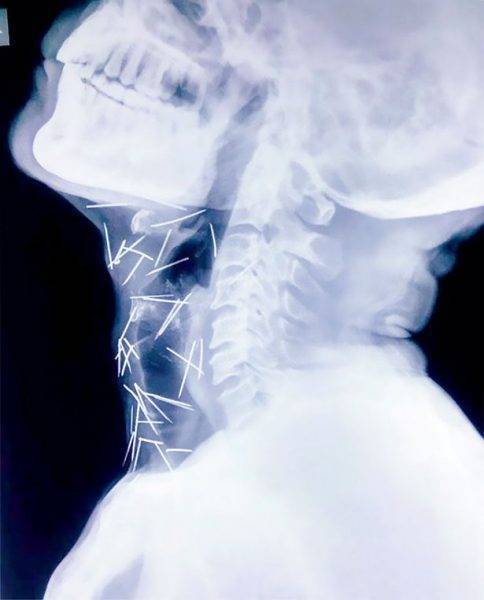

خضع رجلٌ هنديّ لعملية جراحية لاستخراج 75 مسماراً من جسده، تبيّن أنه أدخلها بشكل متعمد.

واظهرت صور الأشعة التي أجراها الأطباء في مستشفي بالعاصمة "نيودلهي”، انتشار تلك المسامير المعدنية في جسد "بادريلال مينا” البالغ من العمر (56 عامًا)

وتم احتجاز "مينا” المقيم في مدينة "كوتا” شمالي الهند في المستشفي، تاركًا عمله في سكة الحديد، ليخضع لعملية جراحية لاستخراج هذا العدد الضخم من المسامير المعدنية.

وبينت الأشعة أن 40 مسماراً في البلعوم، و 25 في القدم الميني، و10 مسامير في أماكن متفرقة من الجسد، والغريب